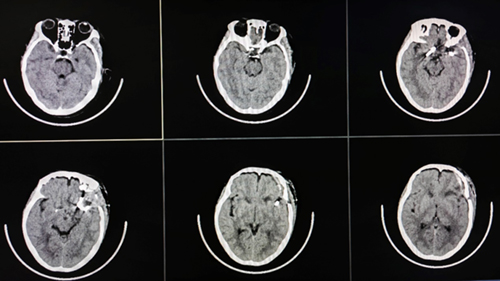

1月11日,在麻醉手术科等科室的配合下,杨伟副主任医师带领神经外科团队共同为患者实施了左侧翼点入路双侧复杂颅内动脉瘤夹闭术。历时4个多小时的“奋战”,经一侧切口入路成功夹闭了双侧2枚难度极高的动脉瘤,术中未发生动脉瘤提前破裂,穿支血管得到良好保护,运动诱发电位监测显示患者上下肢运动功能正常,术中荧光造影显示动脉瘤无显影,载瘤动脉及分支通畅;术后患者一般状况良好,无任何神经功能障碍,复查CT未见术区出血、脑组织缺血等异常表现。